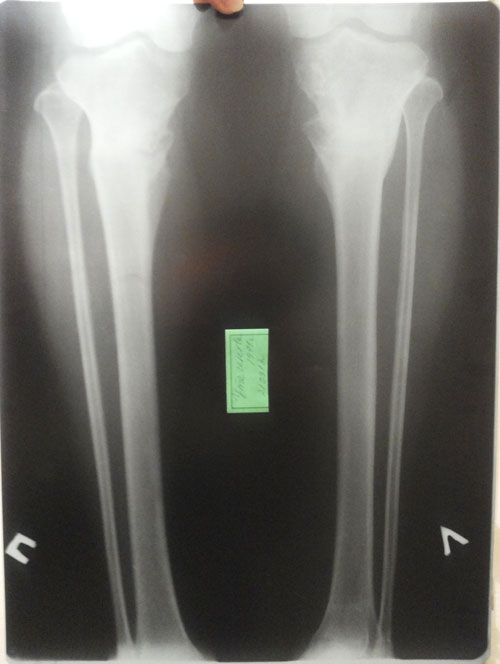

- Диагноз: О- образная деформация нижних конечностей

- Дата операции.: 30.01.2013

- Дата снятия аппаратов.: 04.05.2013

- Срок лечения.: 92 дня

- Оценка результата операции.: Супер